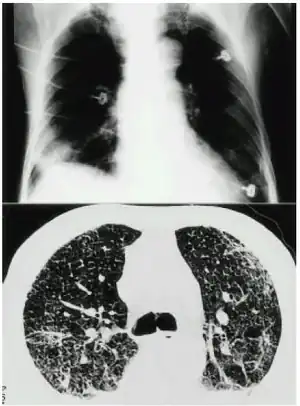

| Mercury inhalation and acute lung injury opn CXR | |